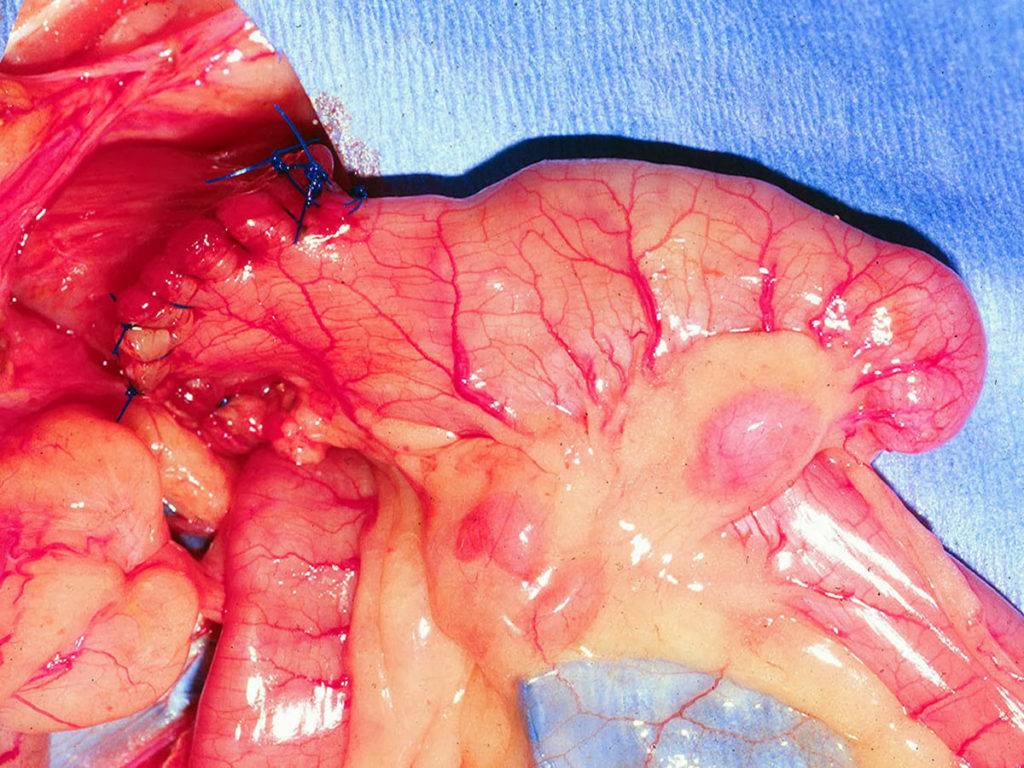

Лечение: извлечение из кишечника инородных предметов

Эвакуация инородных тел из кишечника – непростая и кропотливая работа. Отек слизистой оболочки кишки и рефлекторное сокращение анального сфинктера могут серьезно затруднить процесс. Нередко требуется сначала провести деформацию или разрушение чужеродного предмета, а затем удалить его, применив наркоз. Может понадобиться колотомия (рассечение стенки кишки).

К сожалению, многие пациенты стесняются сразу же обратиться к врачу-проктологу и пытаются извлечь прочно застрявшие внутри тела предметы самостоятельно, руками. Тем самым они еще больше травмируют слизистую кишки.

Применение слабительного также абсолютно недопустимо.

Признаками «застревания» инородного предмета в кишечнике служат боль и спазмы в животе, ложные позывы к дефекации, выделения с кровью и слизью.

После того как врач-проктолог обнаружил инородный предмет в кишечнике, под кожу и слизистую оболочку анального отверстия обычно впрыскивают местное обезболивающее средство. Затем отверстие в заднем проходе увеличивают с помощью анального ретрактората и вынимают инородное тело.

Естественные движения стенки прямой кишки (перистальтика) приводят к смещению инородного предмета вниз, что помогает удалить его максимально безболезненно для пациента.

После того, как было изъято инородное тело, врач-проктолог может провести ректороманоскопию. Это помогает понять: повреждена или нет прямая кишка.

В случае, если не удается отыскать инородный предмет или через задний проход его убрать невозможно, требуется операция

После введения местного или общего наркоза предмет осторожно передвигают к заднепроходному отверстию или рассекают толстую кишку, чтобы удалить инородное тело